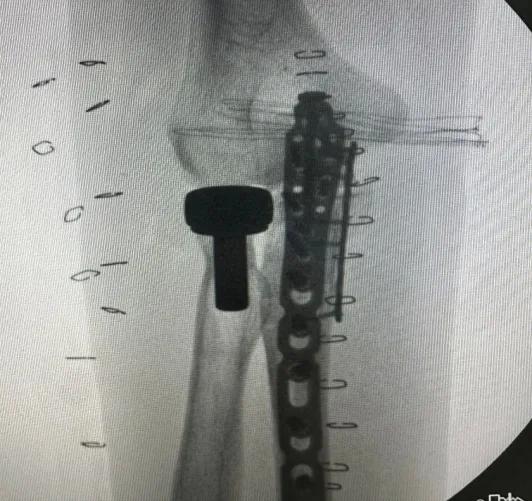

▲ 左肘關節術后

在神經從阻滯麻醉下行

尺骨骨折切開復位鋼板內固定術

和人工橈骨頭置換術